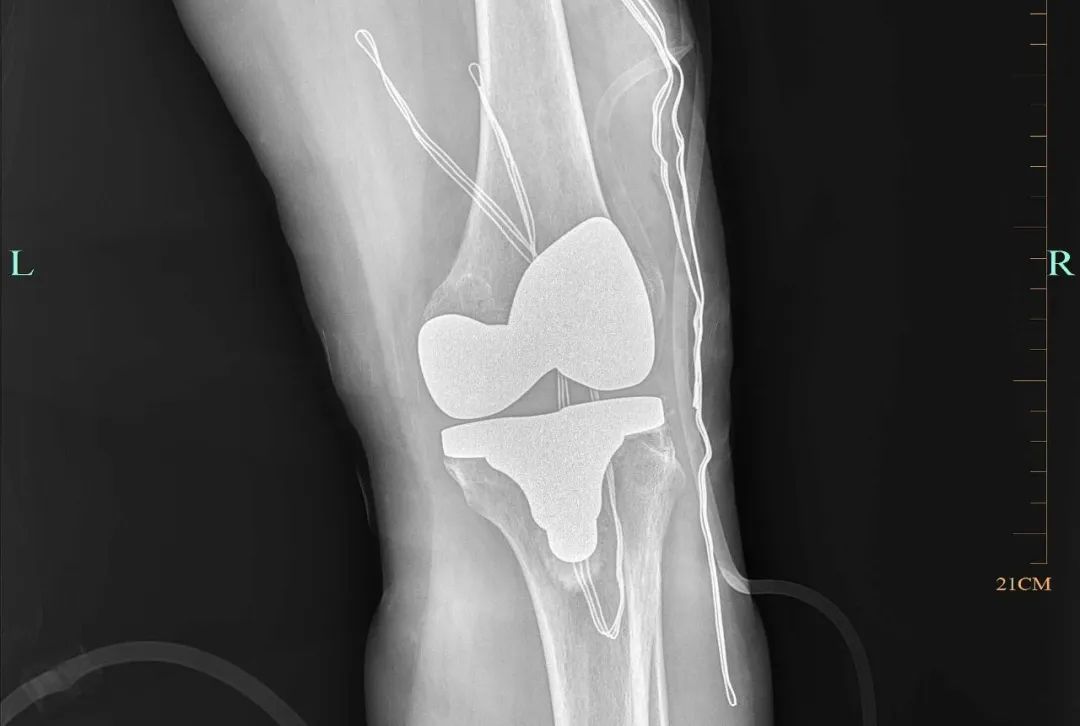

人工膝關(guān)節(jié)置換:是在近代人工髖關(guān)節(jié)成功應(yīng)用于病人后逐漸發(fā)展起來(lái)的一種治療膝關(guān)節(jié)疾病的新技術(shù),是治療嚴(yán)重膝骨關(guān)節(jié)病的切實(shí)有效方法,它能非常有效地根除晚期膝關(guān)節(jié)病痛,極大地提高病人的生活質(zhì)量,在發(fā)達(dá)國(guó)家比較流行。膝關(guān)節(jié)置換就是切除膝關(guān)節(jié)軟骨損壞的表面,并安置一個(gè)人工表面和墊片,構(gòu)成一個(gè)新的關(guān)節(jié),該手術(shù)可以減少患者的疼痛,糾正患者膝關(guān)節(jié)的畸形,恢復(fù)患者膝關(guān)節(jié)的屈伸活動(dòng)。

人工膝關(guān)節(jié)置換術(shù)適合什么樣患者:老年退變性膝關(guān)節(jié)骨性關(guān)節(jié)炎:其癥狀已明顯影響關(guān)節(jié)活動(dòng)和生活能力,經(jīng)保守治療不能改善癥狀者;適用于類(lèi)風(fēng)濕關(guān)節(jié)炎和強(qiáng)直性脊柱炎的膝關(guān)節(jié)晚期病變者;其他非感染性關(guān)節(jié)炎引起的膝關(guān)節(jié)病損并伴有疼痛和功能障礙者,如大骨節(jié)病、血友病性關(guān)節(jié)炎等;創(chuàng)傷性骨性關(guān)節(jié)炎:如粉碎性脛骨平臺(tái)骨折后關(guān)節(jié)面未能修復(fù)而嚴(yán)重影響功能的,因半月板損傷或切除后導(dǎo)致的繼發(fā)性骨關(guān)節(jié)炎等疾??;大面積的膝關(guān)節(jié)骨軟骨壞死或其他病變不能通過(guò)常規(guī)手術(shù)方法修復(fù)者;涉及膝關(guān)節(jié)面的腫瘤切除后無(wú)法獲得良好關(guān)節(jié)功能重建者。什么年齡適合人工膝關(guān)節(jié)置換:膝關(guān)節(jié)置換術(shù)屬于擇期手術(shù),一般適用于50-85歲的人群,最常見(jiàn)的是在60-75歲之間,只要滿足該術(shù)的適應(yīng)癥,同時(shí)保守治療無(wú)效,均可考慮做膝關(guān)節(jié)置換術(shù)。手術(shù)后1-3天可下床活動(dòng),在醫(yī)生指導(dǎo)下盡早進(jìn)行膝關(guān)節(jié)的康復(fù)訓(xùn)練,術(shù)后14天拆線。人工膝關(guān)節(jié)置換術(shù)的使用壽命:雖然人工關(guān)節(jié)假體有一定的使用壽命,到時(shí)可能會(huì)因磨損、松動(dòng)等原因需要翻修,但隨著手術(shù)技術(shù)的不斷提高以及假體材料的不斷進(jìn)步,現(xiàn)代人工關(guān)節(jié)假體的使用壽命正在不斷延長(zhǎng)。